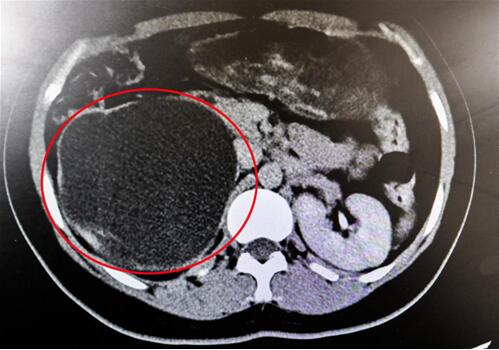

紅圈部分為手術(shù)前腎積水情況。院方供圖

“腎臟就像是一個皮球,因輸尿管完全閉鎖,里面的積水無法排出、越積越多,已經(jīng)把表皮撐得很薄,在造影下甚至都看不清邊緣了!苯纳魅握f,“由于之前手術(shù)的粘連嚴重,手術(shù)難度頗大,腎臟能否保住是個未知數(shù)。”